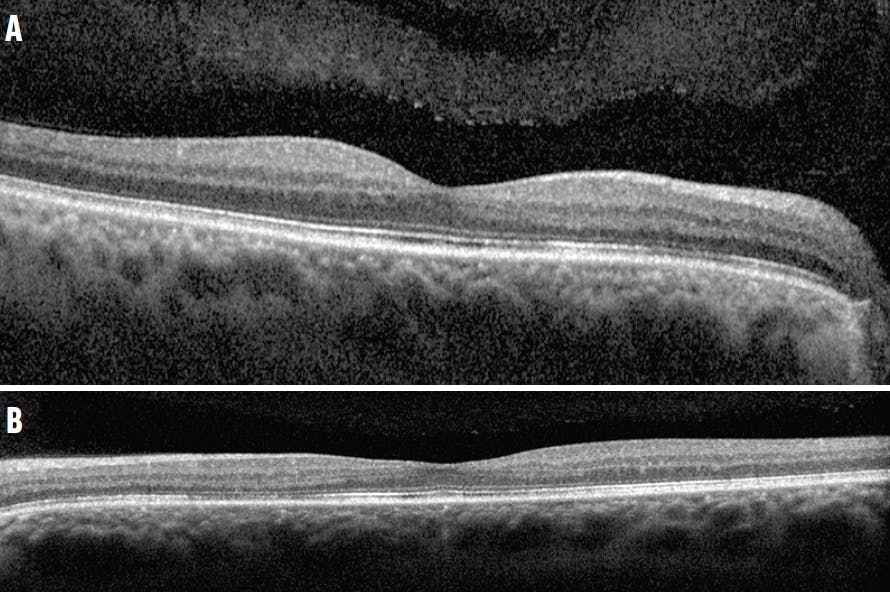

His BCVA was unremarkable in his right eye (6/60 OD), but significantly decreased in his left eye (6/95 OS). His IOP and anterior segment findings were unremarkable. The fundoscopic examination revealed reddish-brown petaloid perifoveal lesions, with the tips pointing toward the center of the fovea (Figure 1). Findings on the optic nerve head were unremarkable. OCT imaging showed subtle disruption of the ellipsoid zone (Figure 2), while OCT angiography (OCTA) showed inner choroidal flow void that corresponded to the abnormal regions on OCT (Figure 3).

<p>Figure 2. OCT showed disruption of the inner segment/outer segment junction (ie, ellipsoid zone) in the right (A) and left (B) eyes.</p>

Figure 2. OCT showed disruption of the inner segment/outer segment junction (ie, ellipsoid zone) in the right (A) and left (B) eyes.